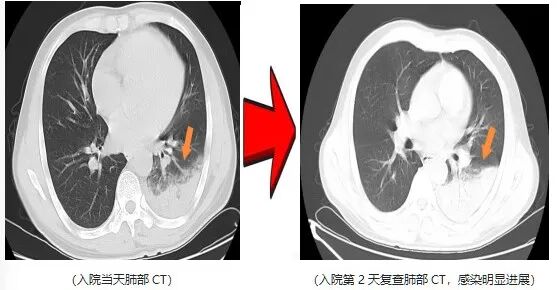

近日,一名爱鸟人士因持续高热、剧烈咳嗽,紧急就诊并收治于杭州萧山区中医院呼吸内科。入院后予以常规抗感染治疗2天,患者高热症状仍反复,最高体温升至40.5℃,伴干咳气促、夜间难以入眠,病情进展后更出现咯血及呼吸衰竭表现。

鉴于患者病情呈重症化趋势,在排除急性肺栓塞等支气管镜检查禁忌证后,医院呼吸内科团队第一时间为患者完善支气管镜检查,同步采集肺泡灌洗液行病原学宏基因组测序,最终锁定致病“元凶”——鹦鹉热衣原体,乐鱼体育官方网站该病原体正是源于患者饲养的宠物鹦鹉。

明确病因后,医护团队给予针对性特效药物干预。仅2天后,患者体温恢复正常,干咳气促、咯血及呼吸衰竭等症状均显著缓解,后续顺利康复出院。